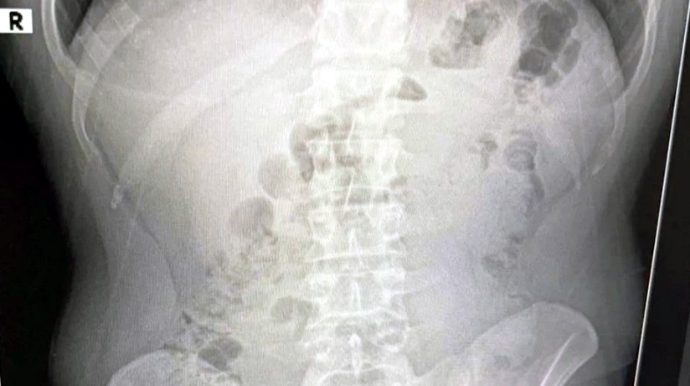

Bildirilib ki, İrandan Türkiyəyə narkotik maddə gətirildiyi barədə kəşfiyyat məlumatı əsasında əməliyyat keçirilib. Texniki və fiziki izləmə nəticəsində, İrandan İzmirin Adnan Menderes Hava Limanına gələn, oradan taksi ilə Uşaka keçdiyi müəyyən edilən üç şəxsin qaldıqları yer müəyyən edilib. Şübhəlilər xəstəxanaya aparılıb. Rentgen müayinələrində onların mədəsində kapsul içində gizlədilmiş metamfetamin aşkar edilib. İran vətəndaşları barəsində məhkəmə həbs qətimkan tədbiri seçib.